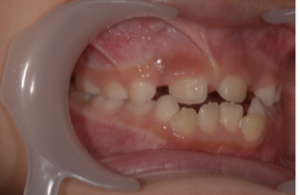

側方からみた方がよく分かると思いますが

治療前

現在

上の前歯2本がだいぶ前方に誘導されているのが分かると思います。

この子は低位舌といい、舌で下の前歯を押すような位置に舌をいつも置いています。プレオルソとあいうべ体操で舌のポジションも改善中です✨